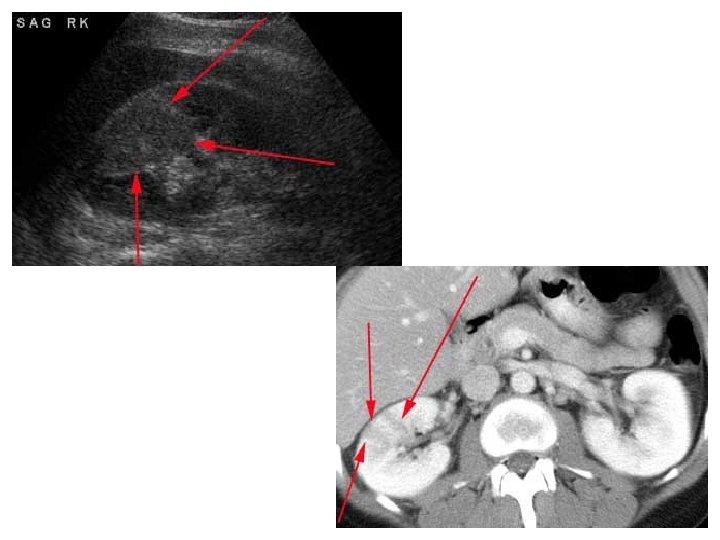

CT • Same basic principle of radiography. • More precise. • Costly. • +/- contrast. • Useful for trauma, stone, tumor, infection.

CT Image features: • Cross sectional images. • Image contrast determined by tissue density +/- contrast. • Better evaluation of soft tissue.